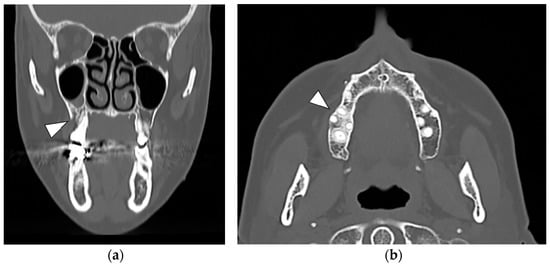

At the 6-month post-operative CT scan, new bone formation was observed in the alveolar socket of the first right upper molar, with a regular trabecular pattern. No signs of bone marrow sclerosis were detected at the right upper molar area (Figure 5a).

At the 1-year CT scan, no bone alterations were present (Figure 5b).

Figure 5. (a) Six-month post-operative CT axial scan with clear aspects of newly formed alveolar bone at the site of surgery (first right upper molar); a residual cortical interruption is maintained in the vestibular aspect without bone focal sclerosis (white arrowhead); (b) Axial CT at one year showing an almost complete continuity of the cortical bone with an alveolar crest width comparable to the contralateral site and resulting from bone repair (white arrowhead); the posterior region of the upper right jaw showed a regular bone architecture and trophism.